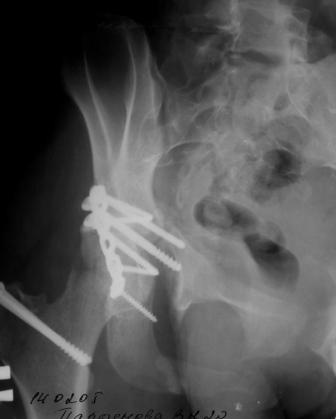

Вторичное смещение вертлужной впадины

Пациентка 18 лет. Травма 19.11.04. D.s.: Закрытыый Т-образный высокий перелом правой вертлужной впадины. Закрытый перелом м\мыщелкового возвышения левой б\берцовой кости. 9.12.04 операция - открытая репозиция, остеосинтез переломам вертлужной впадины. 30.12.05 выписаны на амбулаторное лечение с рекомендациями не вставать на правую ногу. 14.02.05 при контрольном осмотре на Р-граммах выявлено вторичное смещение передней колонны. Клинически подвывиха нет, имеется умеренная приводящая контрактура правого тазобедренного сустава, гипотрофия мышц н\конечностей. Госпитализирована в травмотделение. Выполнено КТ. Имеется смещение передней колонны кнутриЮ диастаз 8 мм. Посоветуйте пожалуйста, что предпринять в данной ситуации.